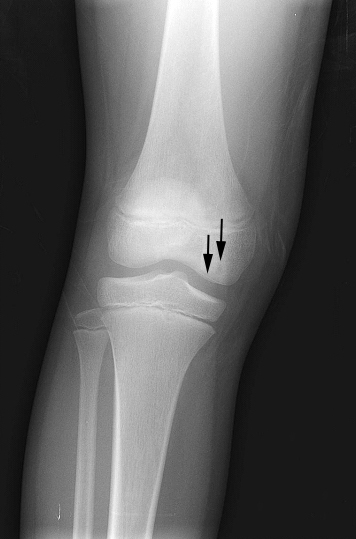

Giant cell tumor of the bone typically arises in the epiphysis of long bones, usually the distal femur or proximal tibia.

Radiology of giant cell tumor of the bone classically shows a “soap-bubble” appearance on x-ray.

Giant cell tumors of the bone are locally aggressive, and they may recur after surgical removal.